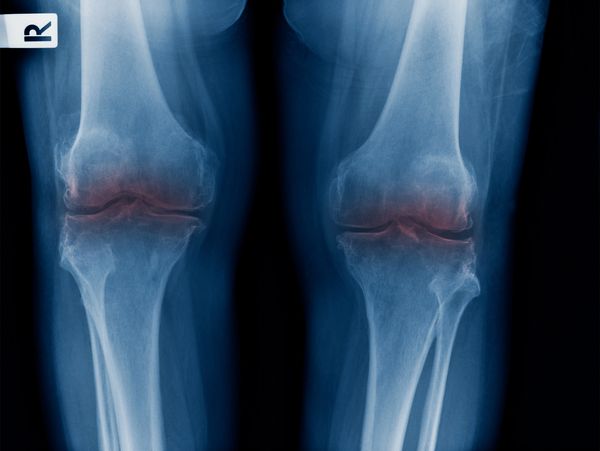

Joint pain can be felt in multiple parts of the body including knee joint pain, sacroiliac joint pain, hip pain and shoulder pain. Age, weight, previous injuries or surgery, overuse and other conditions can be factors causing joint pain.